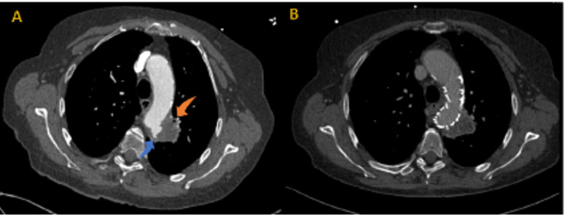

The patient had a prior medical history of a TEVAR (proximally implanted in Zone 3) performed eight months before. This procedure treated a penetrating aortic ulcer (PAU) in contact with the apico-posterior segment of the left upper lobe bronchus, Figure 1.

Figure 1 Pre and post operative axial computed tomography angiography images.

Axial image showing PAU of the thoracic aorta (blue arrow) and its connection with the apicoposterior segment of the left upper lobe bronchus (orange arrow). (B) Post-operative CT scan after TEVAR excluding PAU.